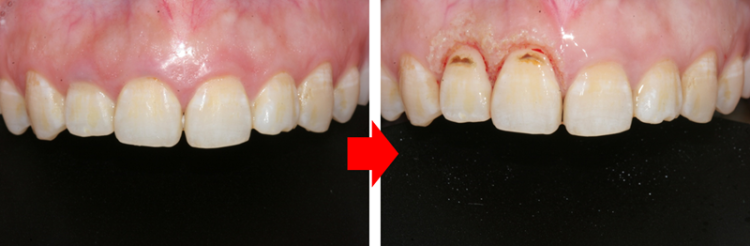

물방울레이저로 치아와 잇몸 사이의 틈에 에너지를 주사해 그 어떤 절개나 봉합 없이 제거를 도와드립니다.

물방울 레이저란 물 분자에 레이저 열을 담은 치료 기기인데요

일반 레이저와는 달리 물방울 분자가 열을 식히고 줄여주기 때문에 출혈과 통증을 현저하게 줄여

부기도 현격하게 완화시키고 물방울레이저가 출시되자마자 사용을 시작해 모든 치료에 접목 시키면서

기술을 향상시켜 진료 수준을 높이게 되었습니다.

3232235521_wVqurUmY_e243630401ba86a1551177115e0e94403b8b8d05.png

치료 전과 치료 후는 이렇게 달라집니다.